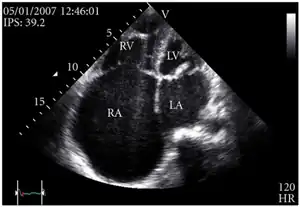

Definitive diagnosis is made by echocardiogram, which is capable of measuring both the presence and the severity of the TR, as well as right ventricular dimensions and systolic pressures.[12]

Chest-Xray: enlarged heart in TR and mitral valve disease Transthoracic echo: enlargement of the right atrium in TR and mitral valve disease

Transthoracic echo: enlargement of the right atrium in TR and mitral valve disease Transthoracic echo: TR (arrow)